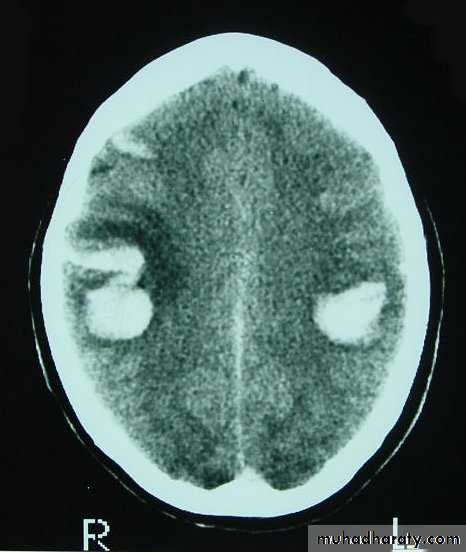

CT scans demonstrates contusions as small areas of haemorrhage in the cerebral parenchyma.

3. Cerebral Contusion